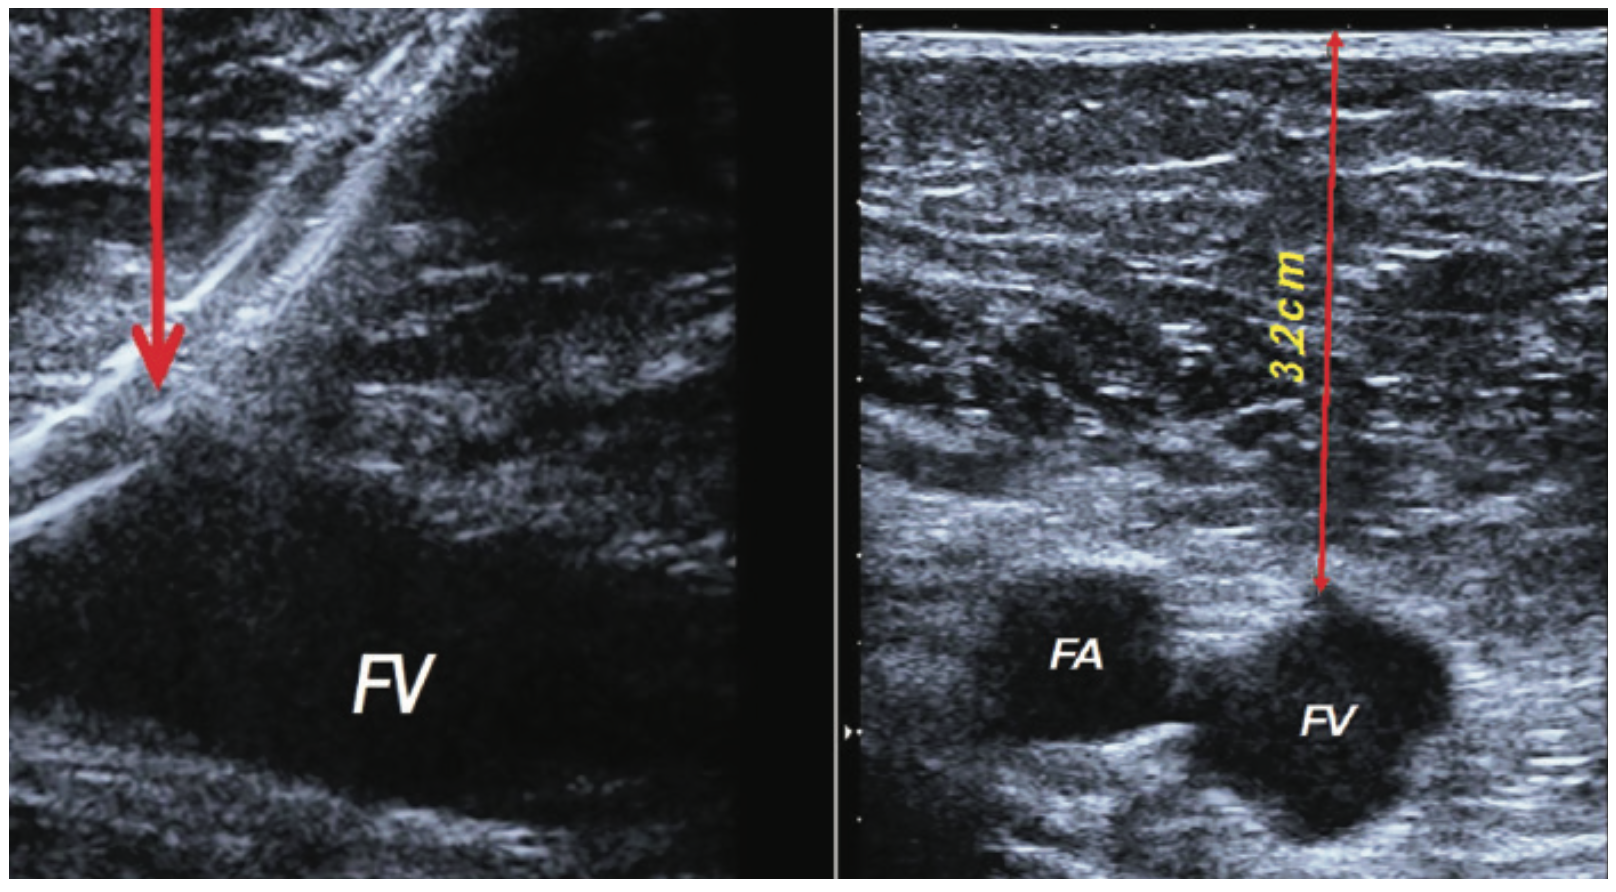

Table 1 describes advantages of ultrasound-guided access, which include visualizing depth and diameter of vessels (Figure 1), assessing flow and disease dynamics, and finding veins that are not visible or palpable. US guidance should be used for peripheral vascular access, especially when by use of palpation or sight, an appropriate vessel for cannulation is unable to be found.2 For some access routes, such as upper arm veins and the popliteal artery, ultrasound-guided access is necessary. For other routes, such as the jugular vein, there is clear evidence that supports the use of US-guided vascular access. US guidance assists in jugular vein access because it allows the operator to avoid accessing the carotid artery and other structures in the neck.1,2

Femoral arterial and venous access is widely used for a wide variety of procedures. For arterial access, US guidance, in conjunction with external rotation of the leg and fluoroscopic marking of the femoral head, can decrease the number of attempts for successful common femoral artery cannulation. It reduces the time to obtain access, the risk of puncturing the wrong vessel or vessel segment, and subsequent vascular complications (Figures 8-9). US guidance helps avoid punctures into the superficial femoral artery or profunda, decreases inappropriate punctures of the femoral vein, and it may prevent sticks above the inguinal ligament. Increasing US experience was associated with a reduced time required for access with US guidance, and operators with greater than 10 procedures have reduced access time and demonstrate a trend toward improved common femoral artery cannulation success.12-15 When using large-caliber sheaths for procedures such as transcatheter aortic valve replacement (TAVR) and endovascular aneurysm repair, US guidance of the vessel ensures placement of the sheath into the center of a large, disease-free vessel segment. This may help minimize procedural complications, improve the technical success of the procedure, and optimize hemostasis.

Fluoroscopic location of the femoral head is an important tool to isolate the femoral artery and vein. However, it is not an accurate landmark on its own, because fluoroscopic guidance does not reduce the number of puncture attempts required to achieve access, puncturing a deep artery at a level identified by a surface marker can be difficult without repeated fluoroscopy, and individual patient anatomy may vary17-19 (Figure 8). Due to these variables and the ability to puncture the target vessel in real time, ultrasound has a defined role for femoral vessel access.